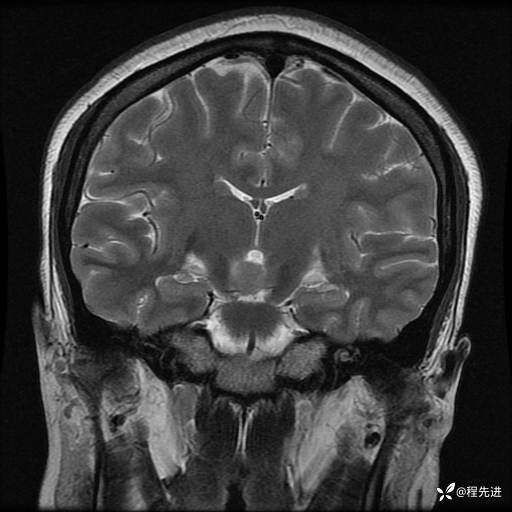

MRI平扫+增强:

T2: